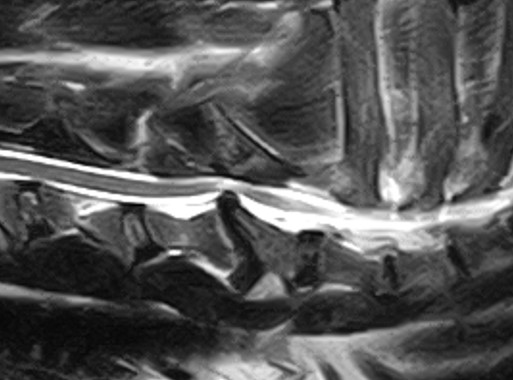

You will probably need to take some X-rays to see what’s going on in the dog’s neck, for which a full general anaesthetic will be required. The use of newer techniques, such as MRI, provides even better views of the problem, but they are also more expensive. The procedure may require a referral to a specialist.

It is possible to determine the nature of the problem in each individual case based on the images obtained. It is important for you to determine exactly where spinal cord compression is occurring so that appropriate treatment can be initiated.